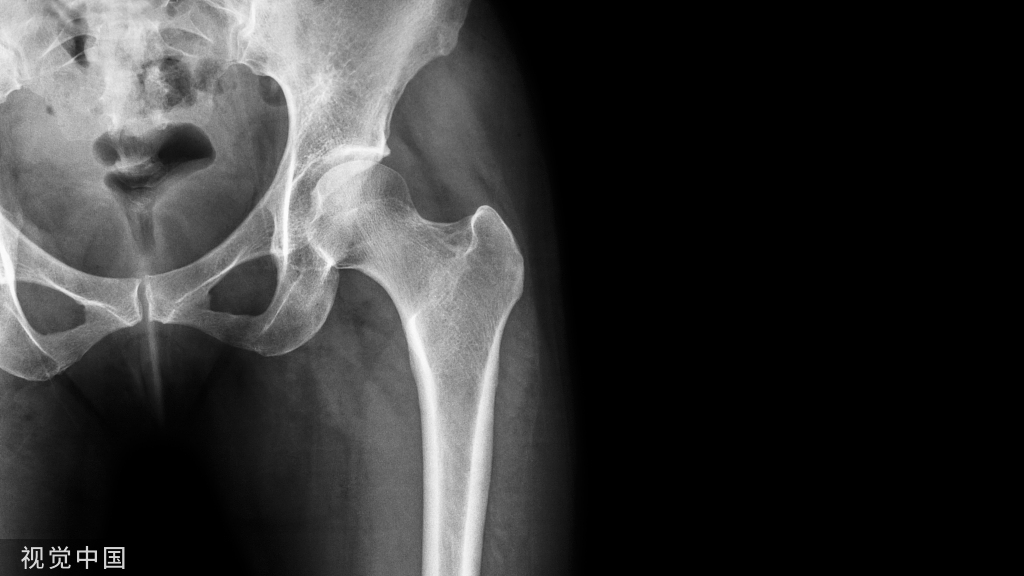

髋关节的X线解剖

常规拍摄正位(见图1)和侧位X线片。

股骨头大部套在髋臼内,表面光滑,为致密的细弧线。头的中心偏后下部有一小凹陷,是股骨头凹,有时可投影到股骨头弧线内侧,显示为小环形透亮圈。

侧位片上,中央的凹窝是髋臼,呈半圆形的致密线。